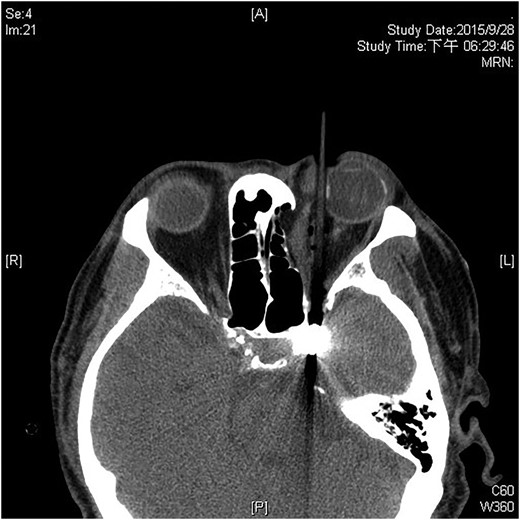

A 60-year-old man was admitted to our medical ward due to aspiration pneumonia. He had a medical history of diabetes mellitus, end-stage renal disease; a tuberculosis bacilli-related thoracic spine infection with paraplegia, and a previous coronary artery bypass graft. During his third day at the hospital, he obtained a ballpoint pen and inserted it into his left eye. On physical examination, the patient appeared to be alert with normal vital signs. The ballpoint pen protruded from his left upper eyelid; it was firmly lodged in his left medial orbit between the globe and nose, causing left eye proptosis (Fig. 1). Neurologic examinations revealed that the patient was neurologically intact except for complete left ophthalmoplegia. Brain CT scanning revealed a tubular foreign body that was located in the anteroposterior plane extending from the orbital apex and directly into the parasellar region (Fig. 2). The metallic portion of the foreign body was entrapped in left optic canal (Fig. 3). There was no evidence of intracranial hemorrhaging or a rupture in the globe (Fig. 4). The patient was treated with high-dose steroids to protect the optic nerve. The plastic ballpoint pen and metallic tip was withdrawn from the orbit smoothly at bedside, and no craniotomy was required. The ballpoint pen had been inserted to an estimated depth of 7 cm through the eyelid and into the orbit. The patient was then transferred to the ICU for close neuro-observation. We initiated intravenous broad-spectrum antimicrobials and vancomycin therapy and continued these medications for three weeks. A psychiatrist was consulted for a complete psychiatric evaluation and suicide prevention. The follow-up CT scan showed no retained foreign bodies or intracranial hemorrhaging (Fig. 5). At the last follow-up examination 2 months after the injury, the patient presented with complete left ophthalmoplegia and blepharoptosis but intact visual function.

The ballpoint pen tip reaches into the parasellar region via the optic canal.